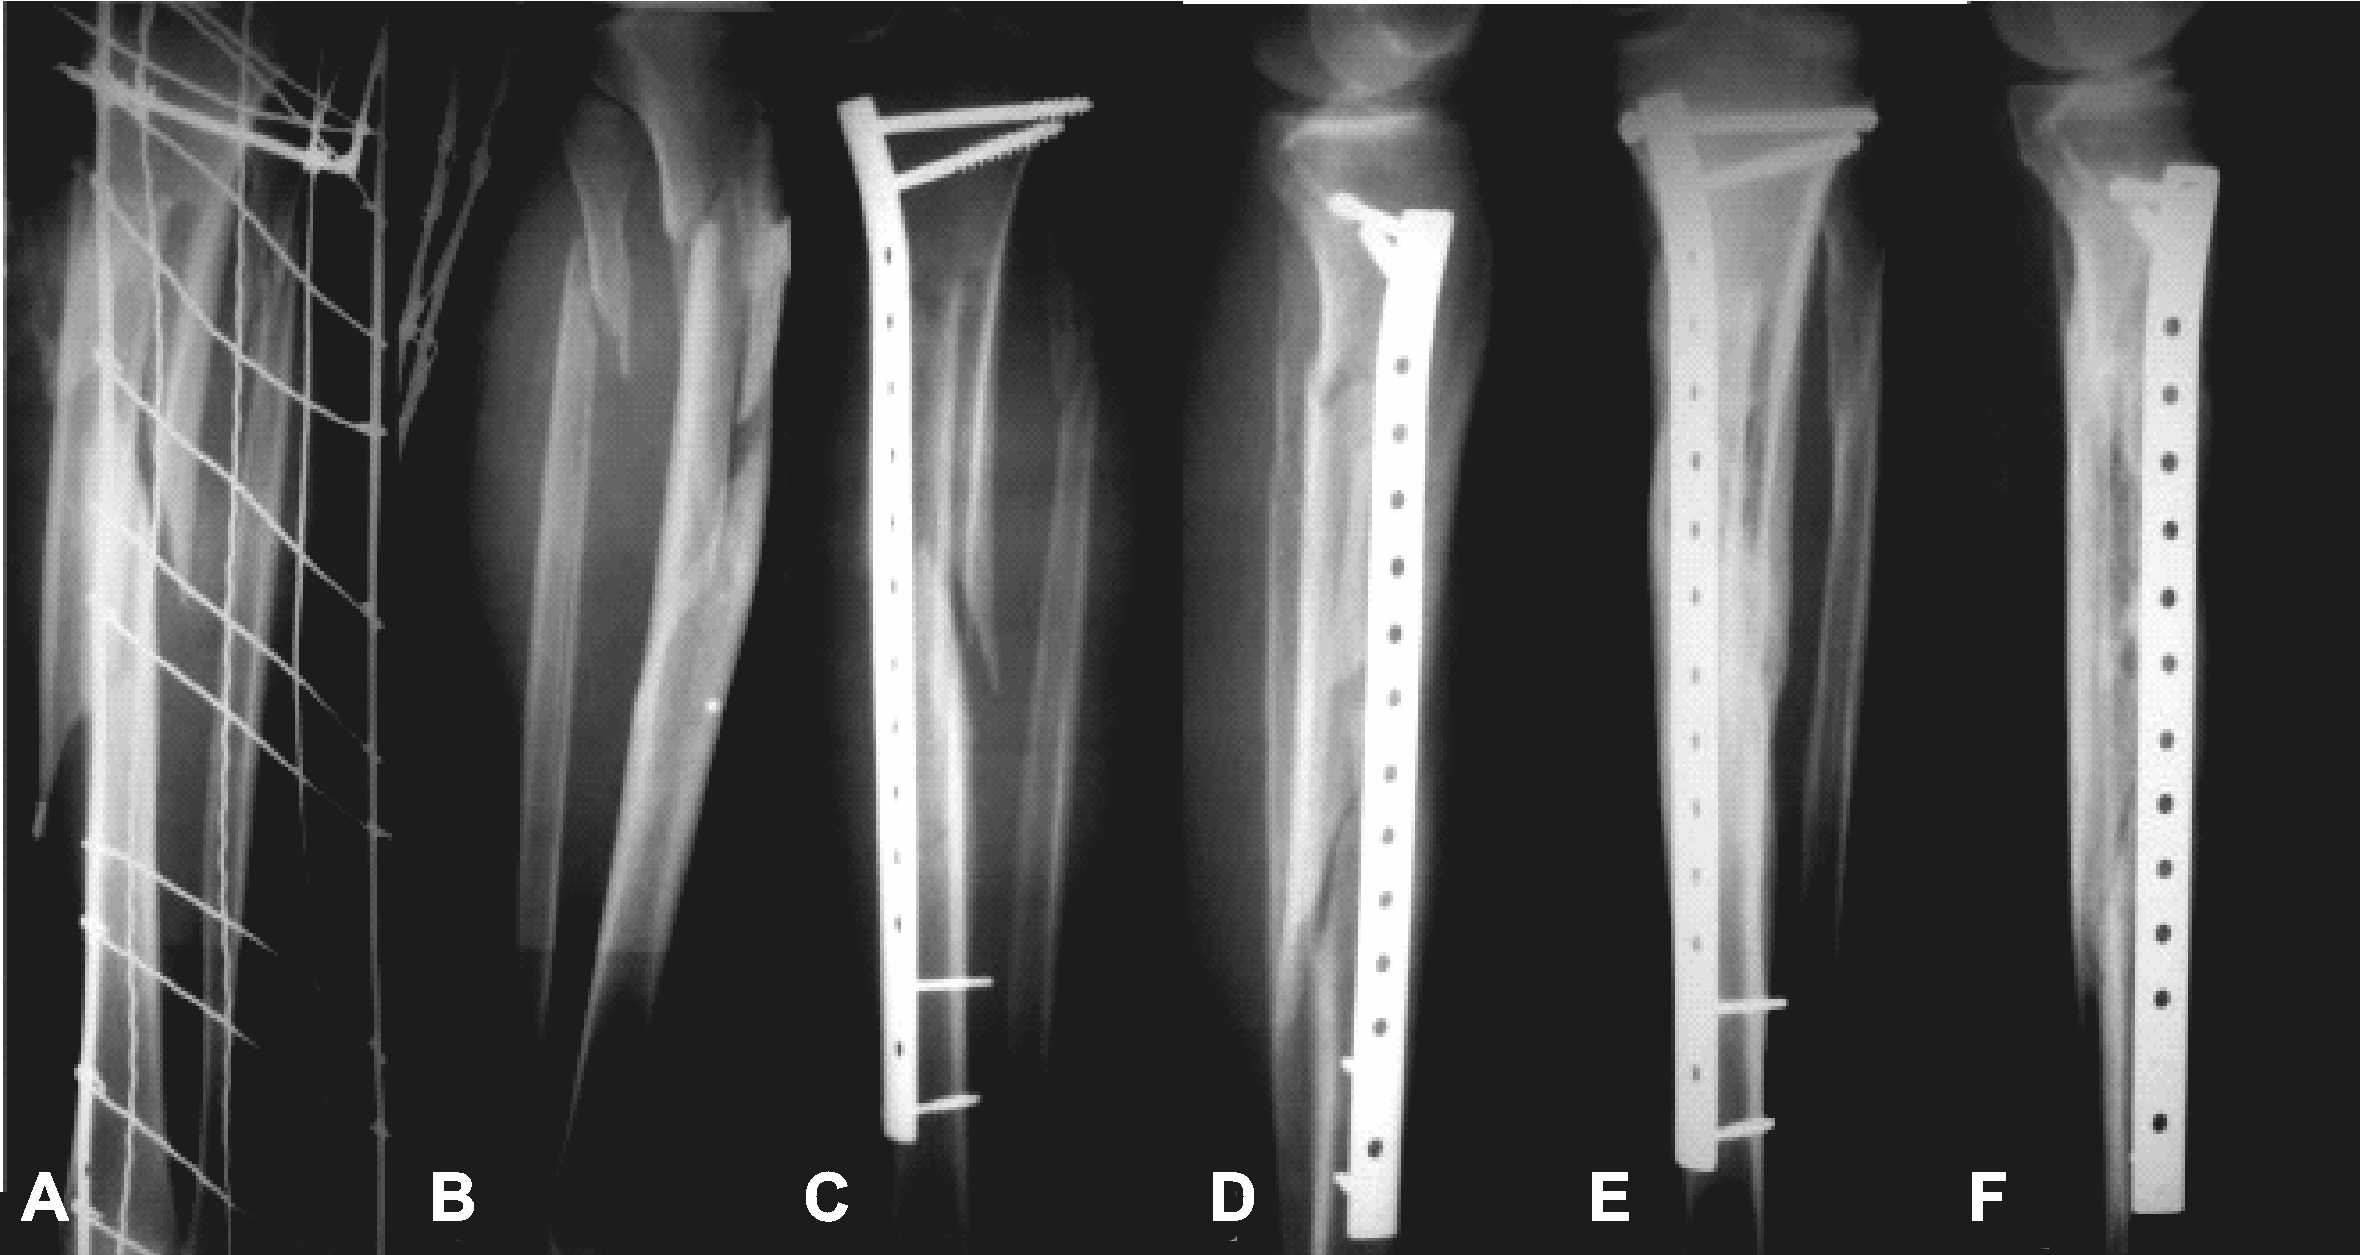

Figure 2 from Minimally Invasive Plate Osteosynthesis with Conventional Meaning Plate Osteosynthesis Plate osteosynthesis is one treatment option for the stabilization of long bones. The surgeon exposes the broken bone and screws a. Plate osteosynthesis is one treatment option for the stabilization of long bones. Plate osteosynthesis is a procedure in which the broken parts of the bone are fixed with a plate. It is widely accepted to achieve bone healing with. Meaning Plate Osteosynthesis.

From www.researchgate.net